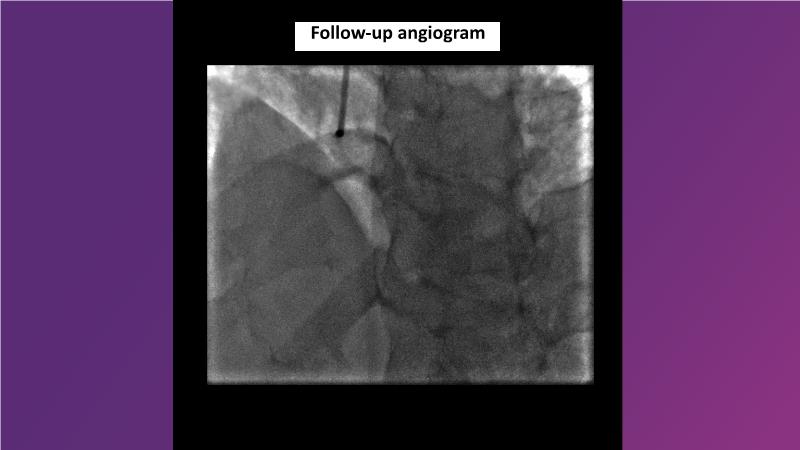

Browse this EuroPCR 2024 session to explore the safety and efficacy of sirolimus-coated balloons from pre-clinical data, review MagicTouch data from real-world populations with case-based examples, and learn about the MagicTouch sirolimus-coated balloon clinical programs. Discover insights and takeaways from the significance of the EASTBOURNE subgroups, and analyze the challenges and opportunities in PCI for diabetic patients.

- To learn from the real world registries and complex cases to understand the practical implications and potential of the device in diverse patient population